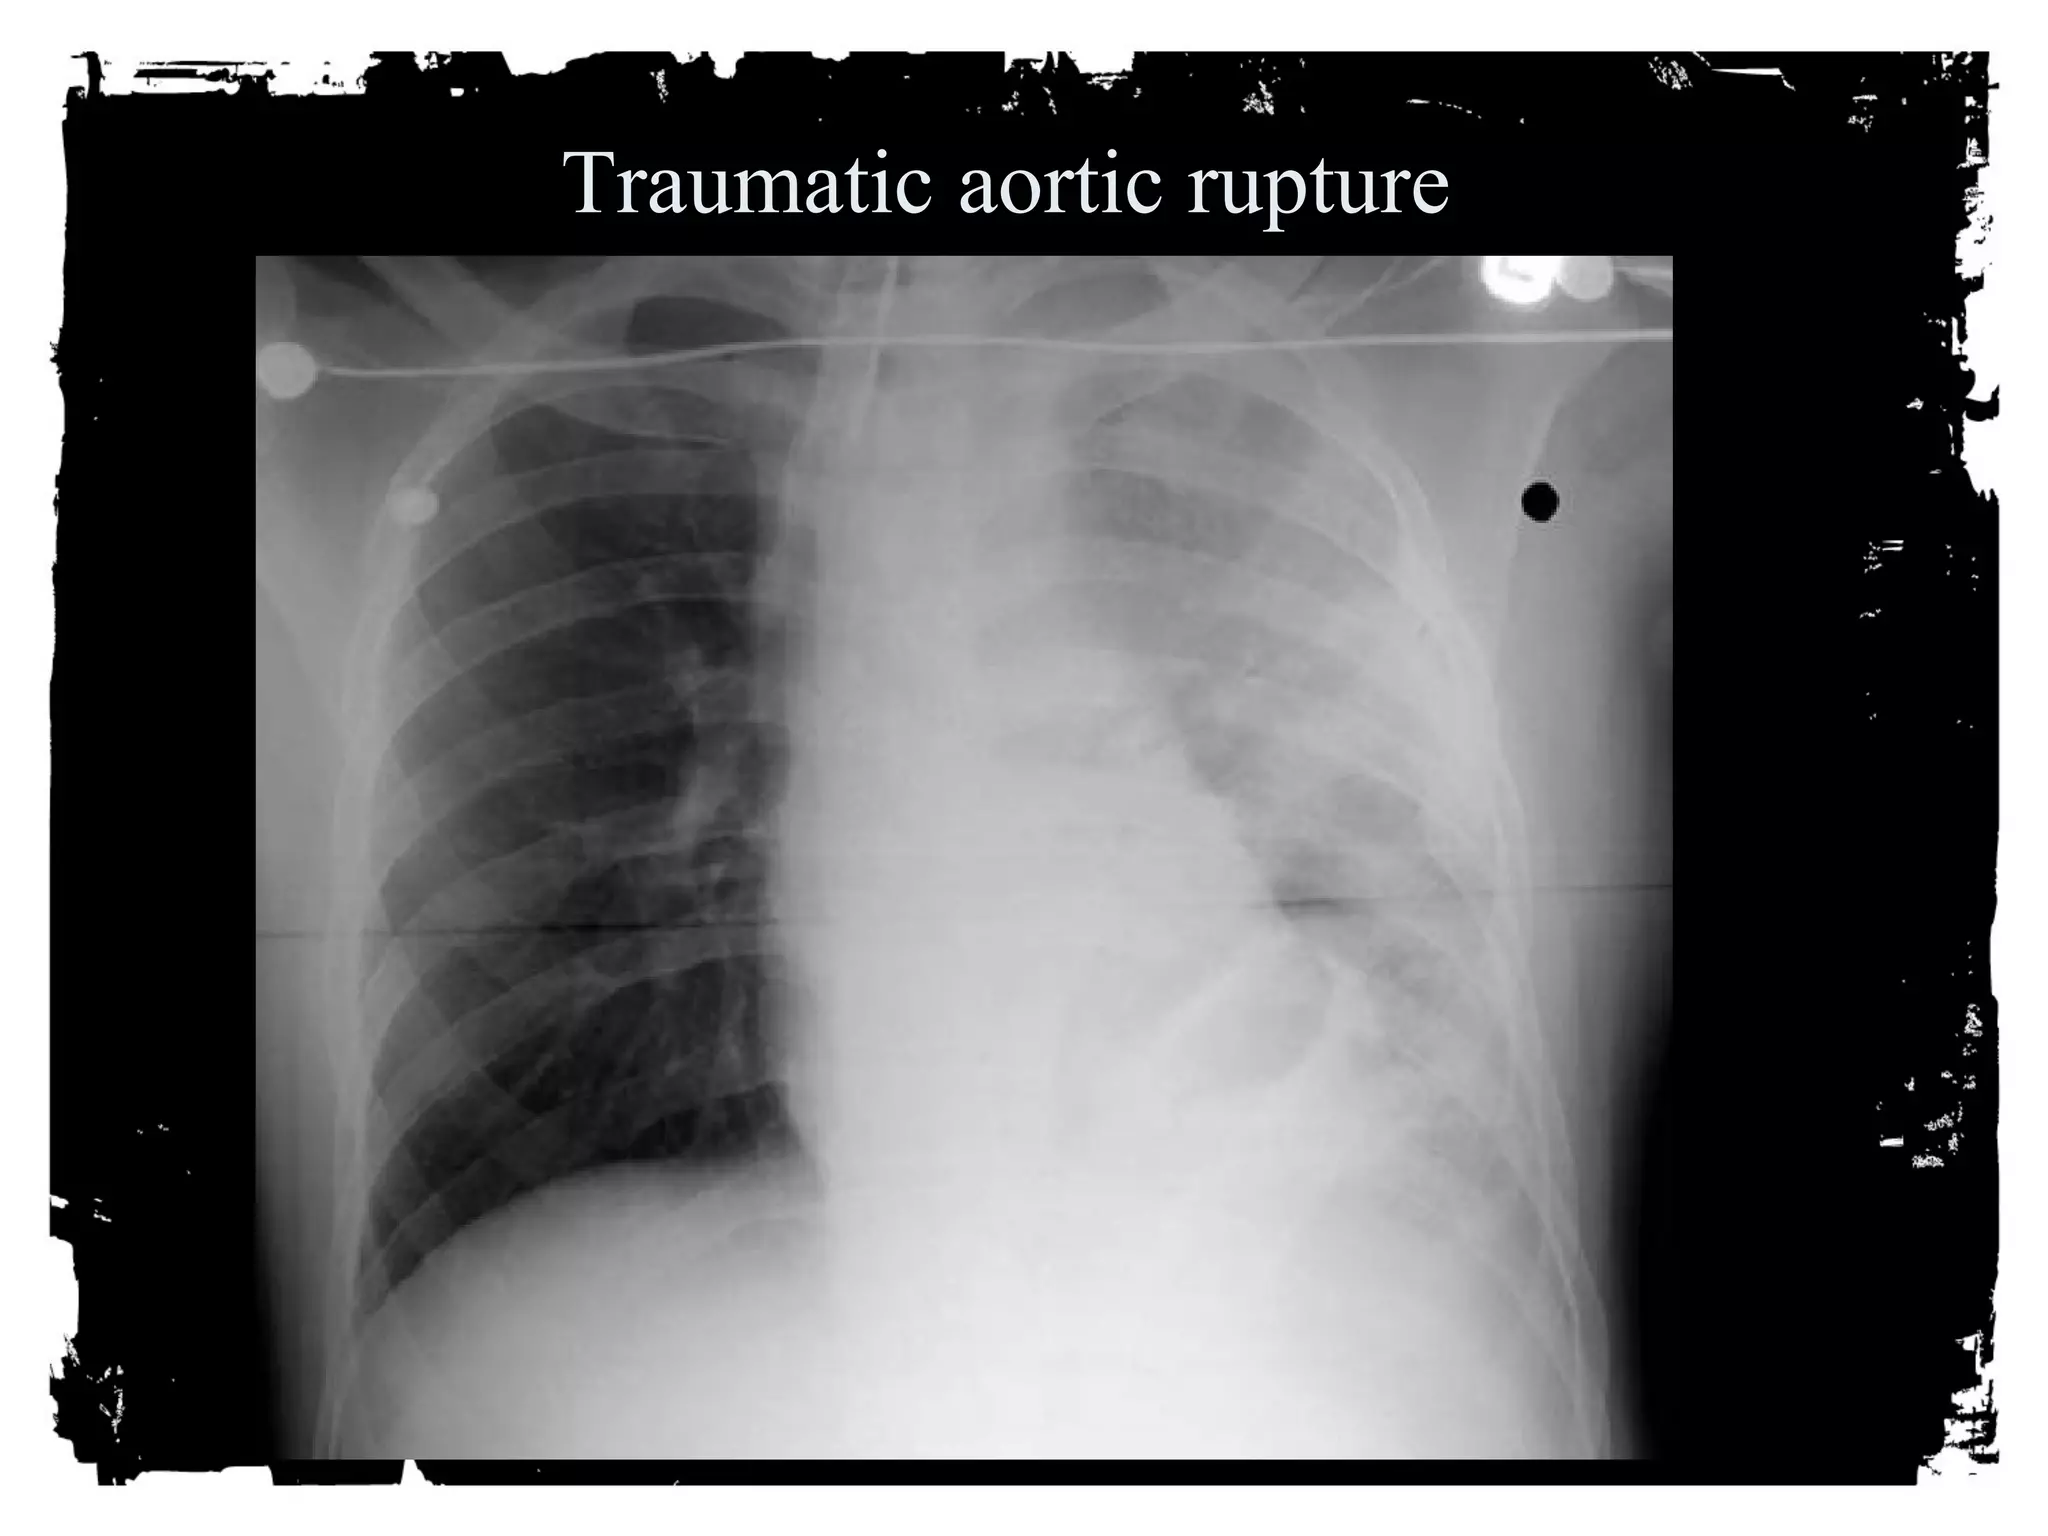

Traumatic aortic rupture

After chest trauma, imaging plays a key role for both,

the primary diagnostic work-up, and the secondary

assessment of potential treatment. Despite its well-known

limitations, the AP chest radiograph remains

the starting point of the imaging work-up. Adjunctive

imaging with CT, that recently is increasingly often

performed on MDCT units, adds essential

information not readily available on the CXR. This

allows better definition of trauma-associated thoracic

injuries not only in acute traumatic aortic injury, but

also in pulmonary, tracheobronchial, cardiac,

diaphragmal, and thoracic skeletal injuries.